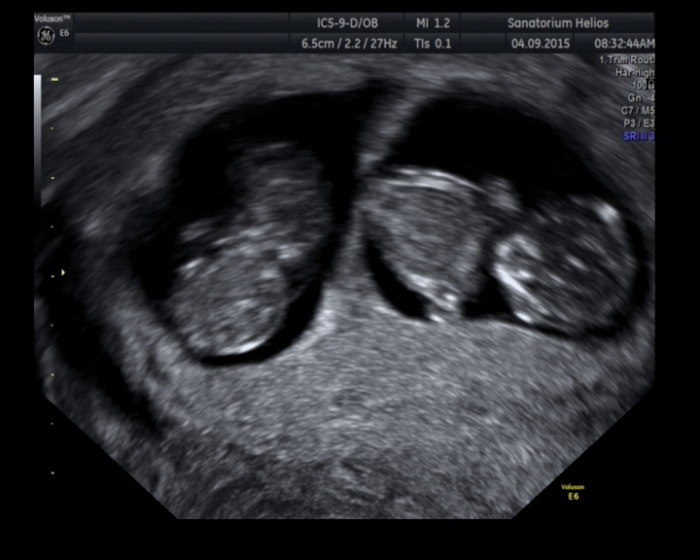

Podle MS bychom měli být dnes 9tt+6, ale podle UTZ jsme 10tt+2 :-) Máme 3 cm. Prckové se tam protahovali, točili, mrskali s sebou.... byla to nádhera. PŘÍZNAKY nulové a miminka se mají fajn

Autor: Luci1 4.9.2015 v 14:25

Za týden další UTZ + odběry krve na screening. Jeden prcek byl o 2mm menší, je mezi něma rozdíl 2 dny, ale prý to vůbec nevadí

Takže jeden odpovídá asi 10tt a druhý 10tt+2